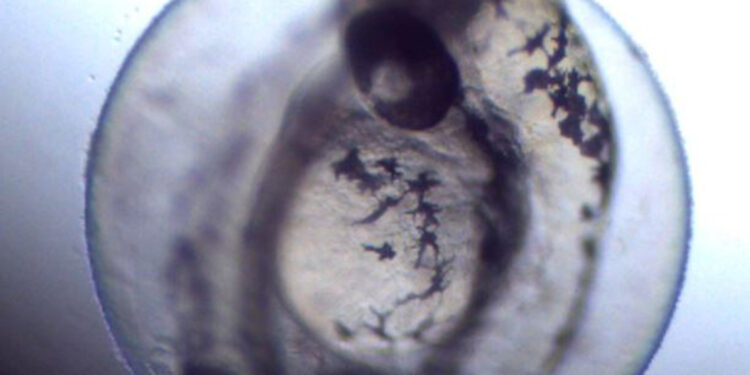

Ankara Üniversitesi Veteriner Fakültesi bünyesinde geçen eylül ayında su canlıları üzerinde deneysel araştırmalar yürütmek üzere ADHAM açıldı. Türkiye’deki veteriner fakültelerinde bir ilk olan merkez, resmi çalışma izni alarak faaliyetlerine başladı. Merkezin genetik araştırmalarında, insan genomuyla yüzde 70 benzerlikler gösteren, insanlarda hastalıklara sebep olan genlerin yüzde 84’ünü taşıyan zebra balığı kullanılacak.

Bilim insanlarına genetik değişiklikleri ve çevresel etkileri nesiller boyu izleme şansı veren, hızlı üreme ve gelişme yeteneği gösteren zebra balığı, ilaçların ve tedavilerin uzun vadeli etkilerini değerlendirmek için ideal ortam sağlayacak. İnsanlar tarafından bilinçsiz kullanılan ilaçlar, kişisel bakım ürünleri, parfüm ve kozmetiklerin etkilerinin, sucul ekosistem üzerindeki etkisini araştırmak ve hayvan, insan, çevreye etkilerini belirlemek için de çalışma başlatıldı.

Aydın, özellikle son yıllarda ilaç geliştirme, aday ilaç maddelerin belirlenmesi araştırmalarında zebra balığının iyi bir model organizma olduğunu kaydederek, “Özellikle insanlarda kullanılan ağrı kesici, antidepresan gibi ilaçların, başta diğer hayvan türleri ile çevre üzerindeki etkilerinin araştırılmasında çalışmalarımızı yürütüyoruz.

Ayrıca, insanların yoğun olarak kullandığı bu ilaçların birlikte kullanılmasına bağlı etkilerin, uzun süreli sonuçlarının araştırılmasında, zebra balıklarını kullanarak etkilerini belirleyeceğiz. Temel hedefimiz, tek sağlık çerçevesinde bu ilaçların tüm ekosistemlerde yaşayan canlılara etkisini belirlemek şeklinde” diye konuştu.